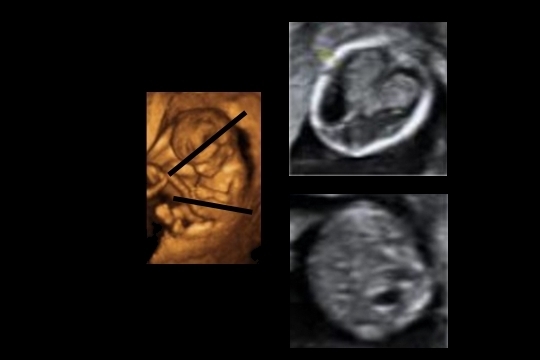

Corte axial o transverso